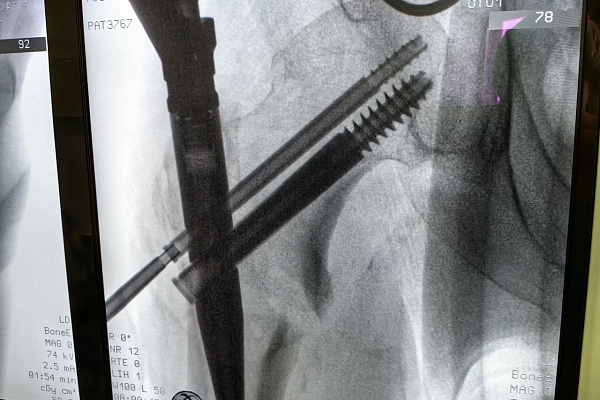

Под постоянным контролем электронно-оптического преобразователя пациенту в место перелома бедренной кости установили интрамедуллярный штифт, которым зафиксировали отломки в нужном положении. Операция выполняется закрытым доступом, через три разреза. Самый большой из них – всего 2 сантиметра.

Для этого больного травматологи-ортопеды выбрали органосохраняющую малотравматичную методику – блокируемый интрамедуллярный остеосинтез.